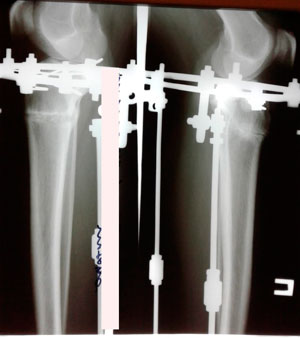

Исходник - 27 лет. Якутия.

Дата операции - 12.07.2019г.

Ротация справа.